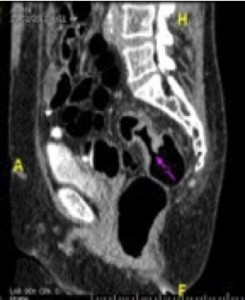

As Dr. Hookey notes the capsule has promise. In a recent multicenter, European trial such a colon capsule endoscopy system was almost as good as colonoscopy. It had high sensitivity (84%) and fair specificity (64%) (Gastrointest Endosc 2011;74:581-9.). Importantly all colon cancers were detected during the 10 hours it took for the capsule to pass. If the capsule is not your speed, consider CT colonoscopy. This technique also requires the colonoscopy preparation but no pill is swallowed and no probe is passed. This image, provided by Dr. Brian Archer, Department of Radiology, Saint John Regional Hospital (Queen’s Meds’88) shows a colon cancer. CT colonoscopy is noninvasive and nearly as sensitive as colonoscopy.

Figure: CT colonoscopy